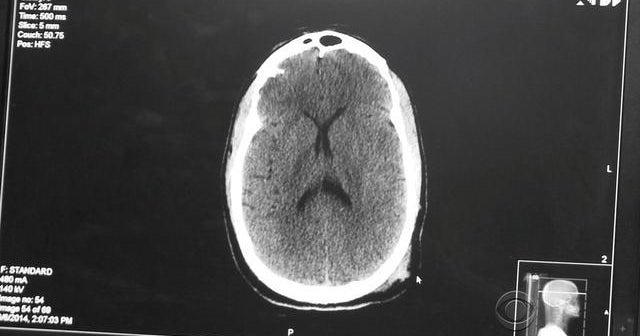

Researchers are developing a way to diagnose concussions by focusing on how eyes track a moving image. As Dr. Jon LaPook explains, the new technique could be key in detecting concussions in patients whose CT scans show no evidence of brain injury.